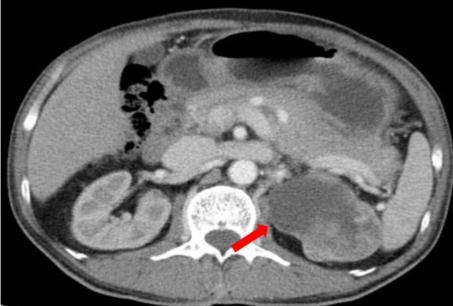

腹盆CT:左肾上部肾实质内可见肿块影,大小约6.6*6.9cm,其内密度不均,与周围肾组织分界不清,增强扫描呈不均匀性强化,考虑肾癌可能。胃体底部小弯侧壁局限性增厚,形成肿块,最大截面大小约5.7*7.6cm,增强扫描强化较均匀,累及浆膜面,肝胃间隙内周围少量肿大淋巴结,大者约2.7*1.9cm,考虑胃癌可能。

PET/CT:贲门部、胃底部及胃体部胃壁增厚、局部软组织密度肿物形成,葡萄糖代谢增高,考虑恶性可能性大(胃癌?)。肝胃之间多发葡萄糖代谢增高淋巴结,考虑转移可能大。左肾上极混杂密度肿物,内伴钙化及坏死,葡萄糖代谢增高,考虑恶性可能性大(肾癌?)。